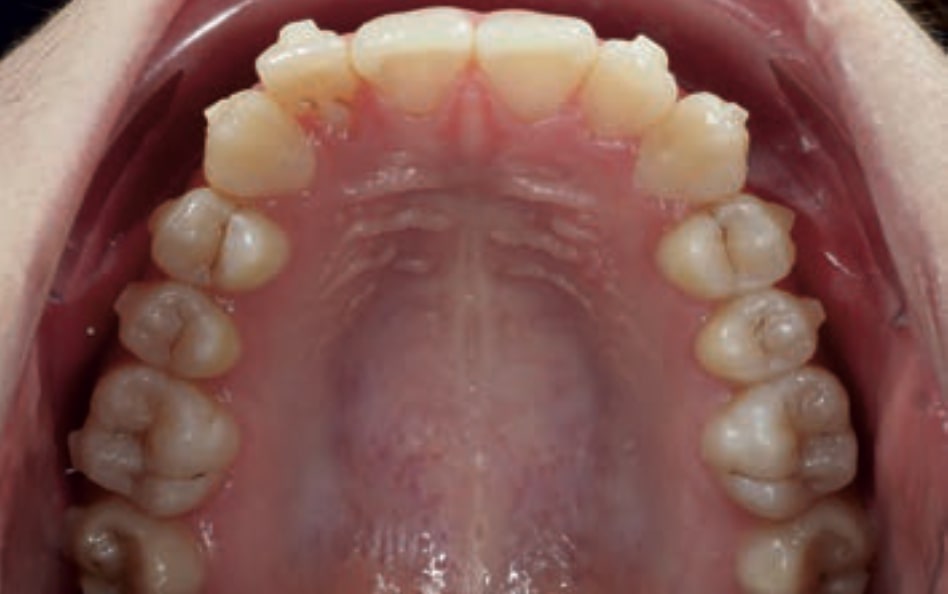

Chief complaint: The patient, a 19-year-old woman, was evaluated to undergo orthodontic treatment using the Angel Aligner Pro system. She presents with a skeletal Class III, mesofacial, with a dental Class III malocclusion and a 2 mm deviation of the lower midline to the left. Teeth 33 and 43 are out of the arch and cortical bone, with a crossbite issue on tooth 33. Fortunately, no functional issues affecting swallowing or breathing have been detected. The patient’s motivation for starting treatment was a general review of her dental and aesthetic health. The soft tissue analysis reveals mandibular protrusion that influences her facial profile. This diagnosis highlights the need for a comprehensive approach to address dental and skeletal misalignments, improving both the patient’s functionality and facial aesthetics.

- Dental Class III, 2 mm deviation of the lower midline to the left. 33 and 43 out of the arch and the cortical bone.

- Distalize third and fourth quadrant

- Distalization of the Third and Fourth Quadrants: Move the teeth distally in these quadrants to achieve a Class I relationship using the A8 protocol, improving the patient’s dental alignment and occlusion.